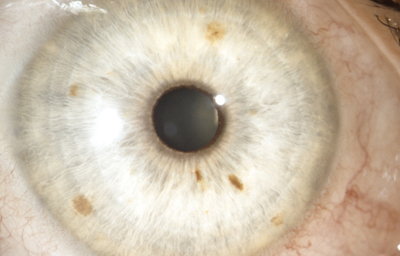

Síndrome de Waardenburg (Bilateral) PAX3 (Neurocristopatia) (22,23)Es un grupo con unas condiciones genéticas raras por lo general de herencia autosomica dominante, es una forma de albinismo irregular, fluctuante; tienen epitelio pigmentario normal y visión normal; sinembargo en el tipo II y IV hay también herencia autosomica recesiva.- Se describen 4 tipos en este síndrome.

El tipo 2: es el mas frecuente siendo raro, Pueden tener mechón blanco en el cuero cabelludo, manchas blancas en la piel y heterocromia del iris por hipopigmentación bilateral. Mutación del MITF( factor de transcripción asociado a microoftalmia). Aquí se describe también, el Síndrome de Tietz,(descrito en 1963 por Walter Tietz) semejante al tipo 2 con Hipoacusia neurosensorial e Hipopigmentación generalizada de la piel a diferencia de los parches en el Waardenburg. Los ojos tambien son afectados, con Iris claro e hipopigmentación en el epitelio pigmentario de la retina. Autosómico dominante ( Mutación MITF)4

OI

Foto tomada de internet